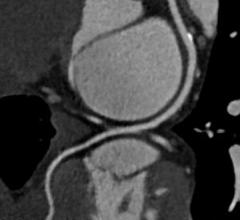

Coronary computed tomography angiography (CCTA) is a noninvasive tool that can be used for identifying myocardial…

Feature | Dave Fornell

There are currently three major trends in cardiovascular computed tomography (CT) technology — lowering radiation dose…